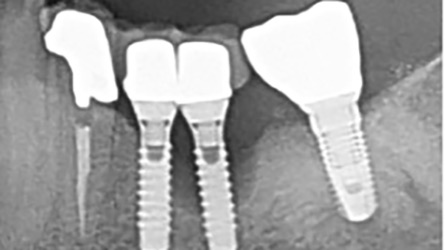

Complete Digital Workflow for Mandibular Full-arch Implant Placement and Temporalization by “Smile in a Box”

Abstract Modern oral implantology requires comprehensive diagnosis, intricate planning, and precise execution to achieve desired prosthetic and functional outcomes to meet patients’ and clinicians’ expectations. In this context, digital dentistry has been adopted as an excellent service, especially for complicated full-mouth rehabilitation cases, to which the implant all-on-6 concept has become an established treatment option. … Read more